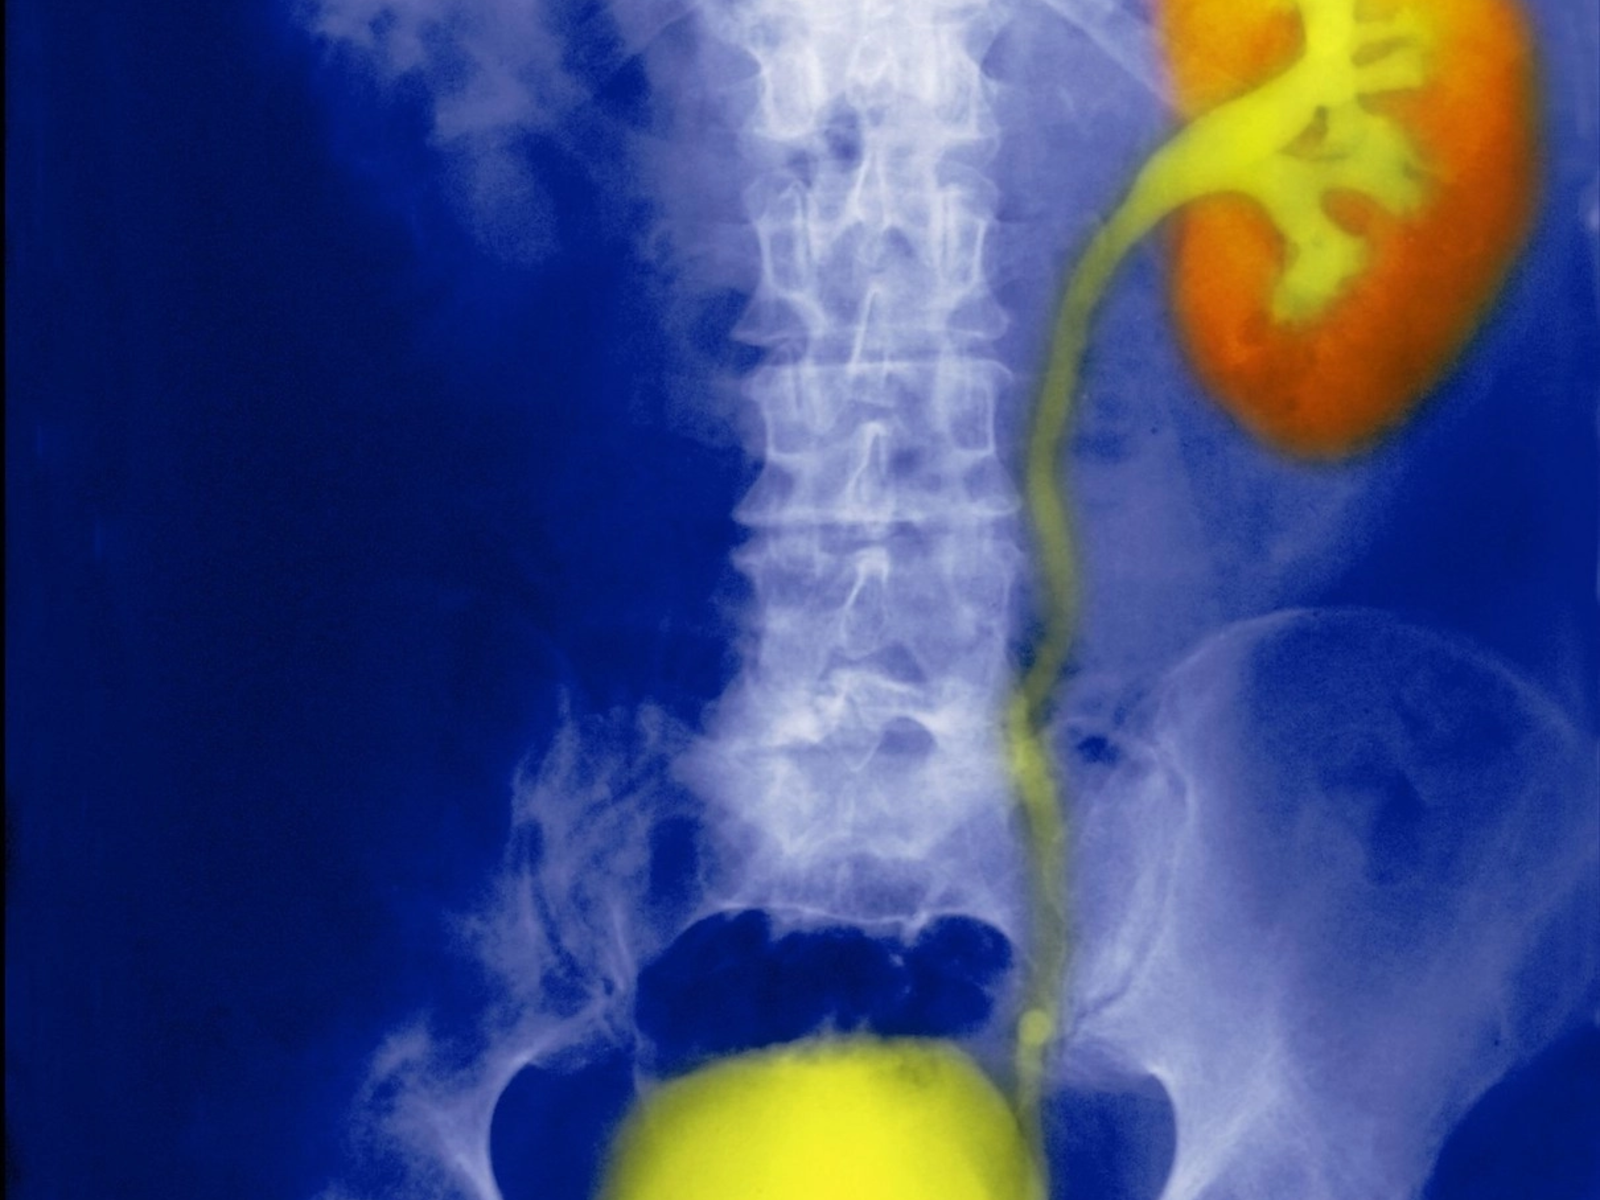

O echipă de cercetători de la Institutul European de Oncologie și Universitatea din Milano a făcut o descoperire importantă care ar putea schimba modul în care sunt diagnosticate și tratate formele agresive de cancer la vezica urinară.

Studiul, publicat în revista Nature Communications, a identificat o proteină numită Numb care joacă un rol crucial în dezvoltarea tumorilor. Această proteină, care există în mod normal în țesutul vezicii urinare, lipsește la peste 40% dintre pacienții cu cancer vezical, scrie La Repubblica.

Un aspect important al studiului este că a schimbat înțelegerea modului în care evoluează acest tip de cancer. Până acum, medicii credeau că tumorile superficiale și cele profunde sunt două boli diferite. Noua cercetare arată că, de fapt, este vorba despre același proces care evoluează în timp, ghidat de mecanisme moleculare care pot fi combătute cu medicamente specifice.